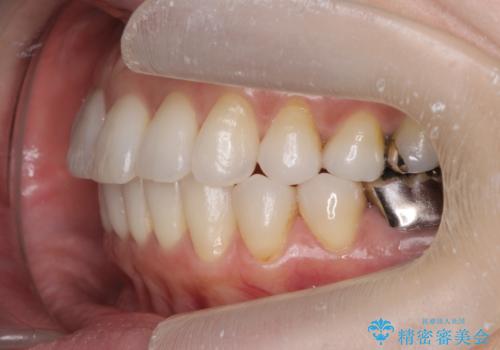

- 突き出た前歯の角度を改善したい、と矯正治療を希望され来院されました。

抜歯を行いワイヤー矯正で2-3年程度の時間をかけて、しっかり前歯を後方に移動させるか、

抜歯を行わずにIPR(歯の間に空隙を設ける)で可及的に角度の改善を行うか、

2通りの治療方針をご提案しました。

治療期間が約半年で行うことができ、歯を抜かずにマウスピース矯正で可及的に前歯の角度を改善する治療方針を

奥歯の状態等も鑑みて選択されました。

約半年で大きく前歯の角度を改善することができ、抜歯を行わない矯正治療の結果に大変喜んでいただくことができました。